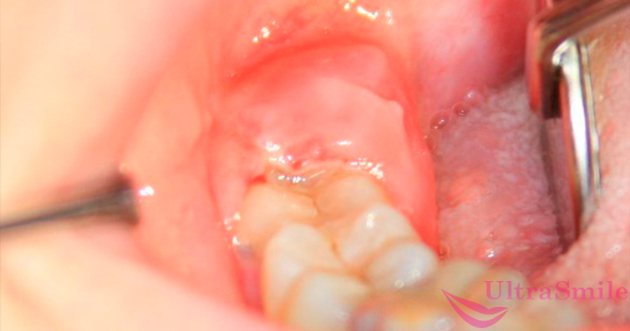

Прорезывающийся зуб мудрости

Почему еще может одновременно болеть голова и челюсть? Если у вас начал резаться зуб мудрости, что обычно происходит во взрослом возрасте, то очень может быть, что именно он стал виновником проблемы. Массивный третий моляр мучительно долго проходит через челюстную кость, задевает нервные окончания, отчего возникает болевой синдром. Однако сказать, где точно болит, очень сложно, потому что ощущения размыты, часто они захватывают челюсть, на которой режется «восьмерка», а также отдают в голову и виски.

Если вы стали обладателем «восьмерки», то обязательно покажитесь стоматологу и сделайте рентген. Очень часто третьи моляры оказываются ретинированными и дистопированными, что приводит к серьезным последствиям для всей полости рта, если их не удалить: они вызывают скученность зубного ряда и патологии прикуса, провоцируют острое гнойное воспаление десневого капюшона (перикоронарит), разрушают соседние единицы, прорезываются уже пораженными кариесом и пульпитом – все это тоже может приводить к болезненным ощущениям в области головы и челюсти.